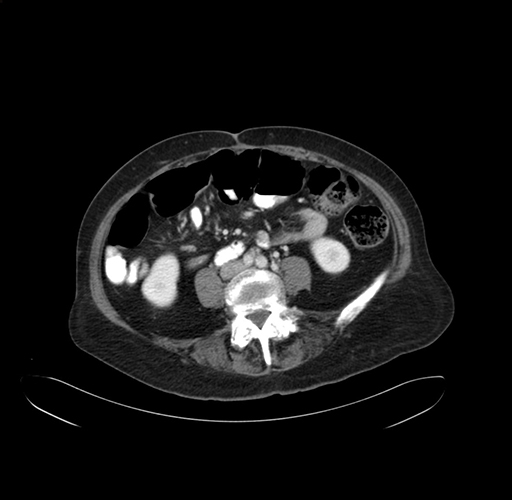

Pre-Chemo: Axial Venous